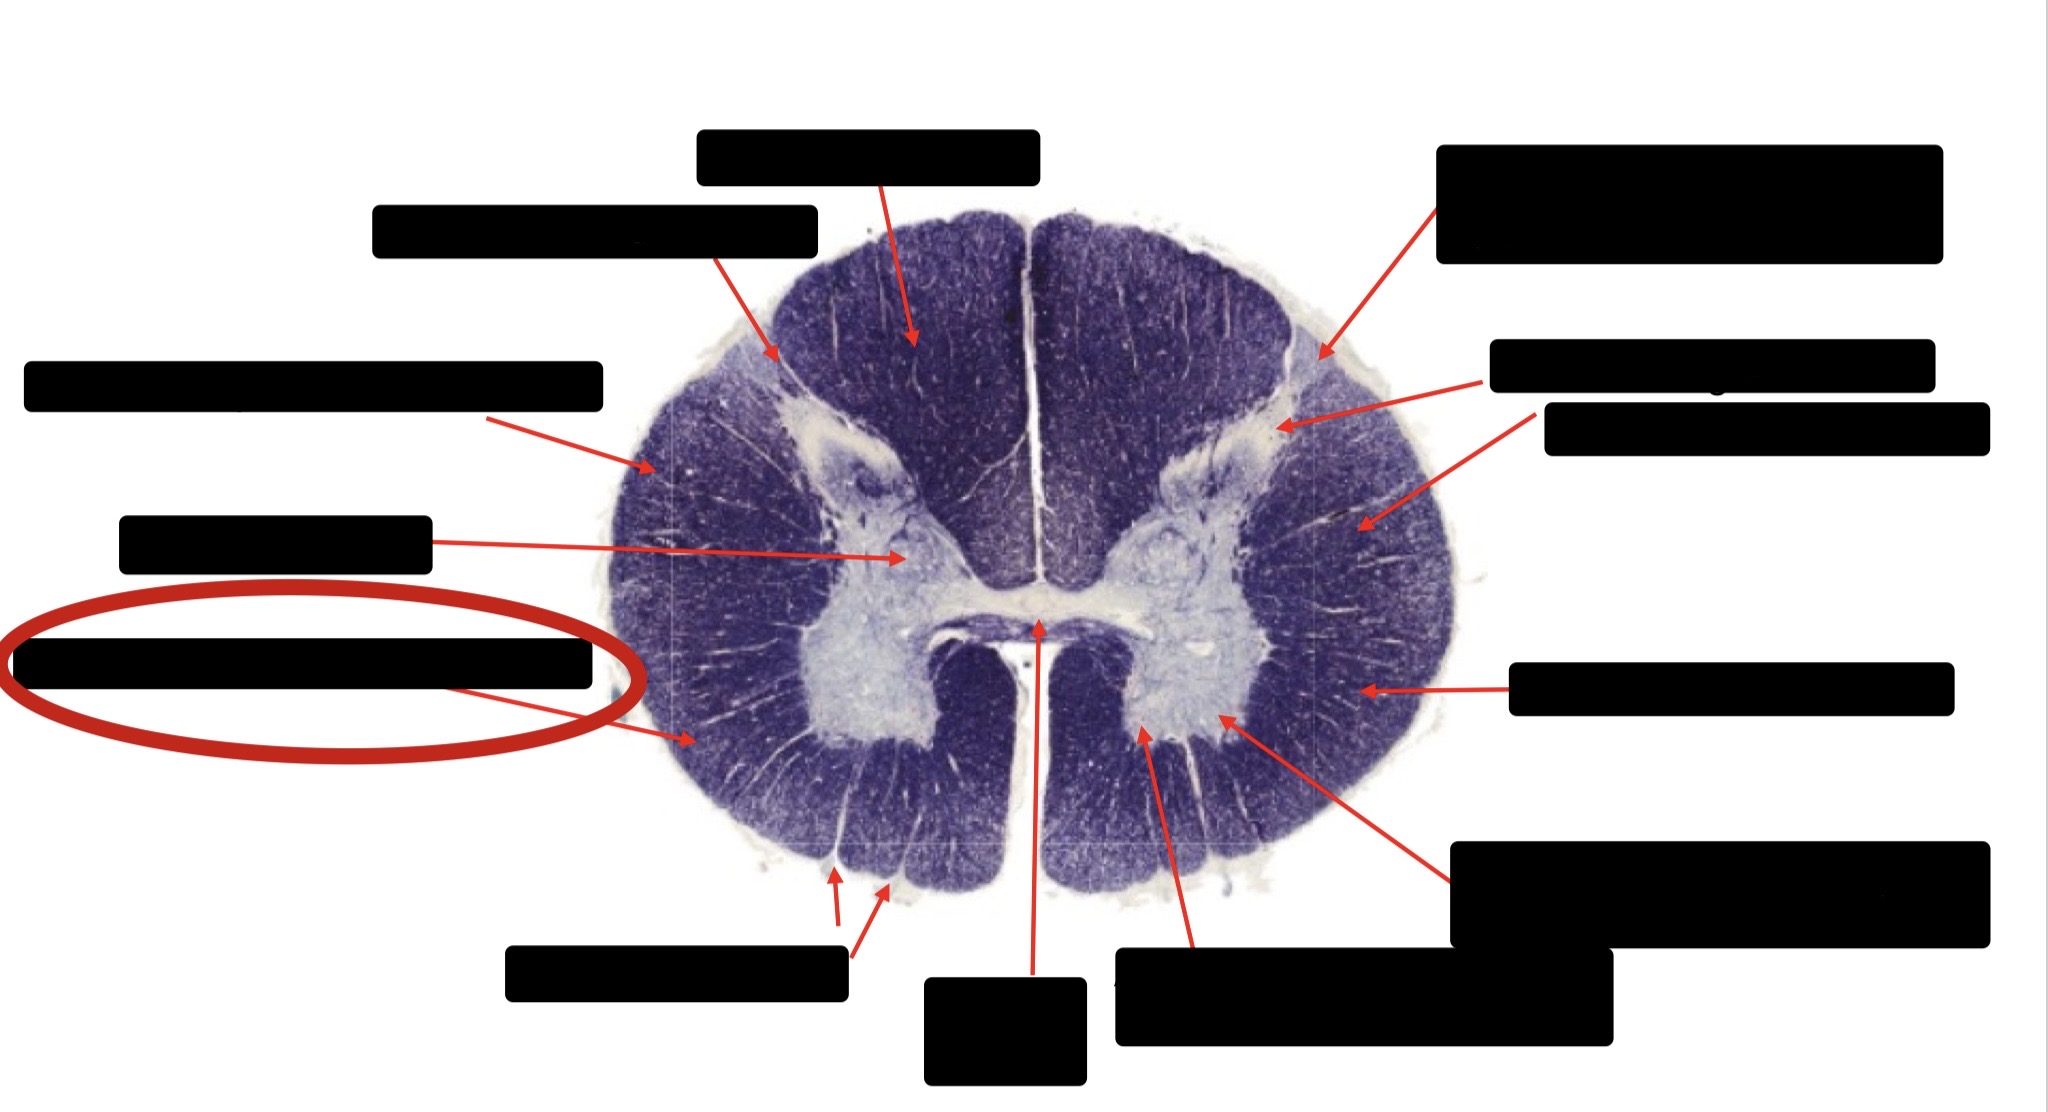

Dorsal Rootlet

Posterior Spinocerebellar Tract

Lateral Corticospinal Tract

Anterior Spinocerebellar Tract

Spinothalmic Tract

Central Canal

Anterior Corticospinal Tract

Posterior Column (Fasciculus Gracilis)

Posterior Column (Fasciculus Cuneatus)

Substantia Gelatinosa

Accessory Nerve Fibers

Anterior Horn Motor Fibers (Accessory Muscles)

Anterior Horn Motor Fibers (Proximal Muscles)

Ventral Root Fibers

Anterior Horn Motors Neurons (Proximal Muscles)

Posterior Columns (Joint Position, Vibration, Pressure)

Fasciculus Cuneatus

Fasciculus Gracilis

Dorsal Root

Dorsal Spinocerebellar Tract

Ventral Spinocerebellar Tract

Lateral Spinocerebellar Tract (Pain & Temperature)

Ventral Root

Anterior Horn (Motor Neurons)

Distal Limb Movements

Lateral Corticospinal (Pyramidal Tract)

Rubrospinal Tract

Axial & Proximal Limb Movements

Lateral Reticulospinal Tract

Vestibulospinal Tract

Ventral Reticulospinal Tract

Tectospinal Tract

Ventral Spinthalamic Tract (Pressure Touch - Minor Role)

Ventral (Uncrossed) Corticospinal Tract (Distal Limb Movements - Minor Role)